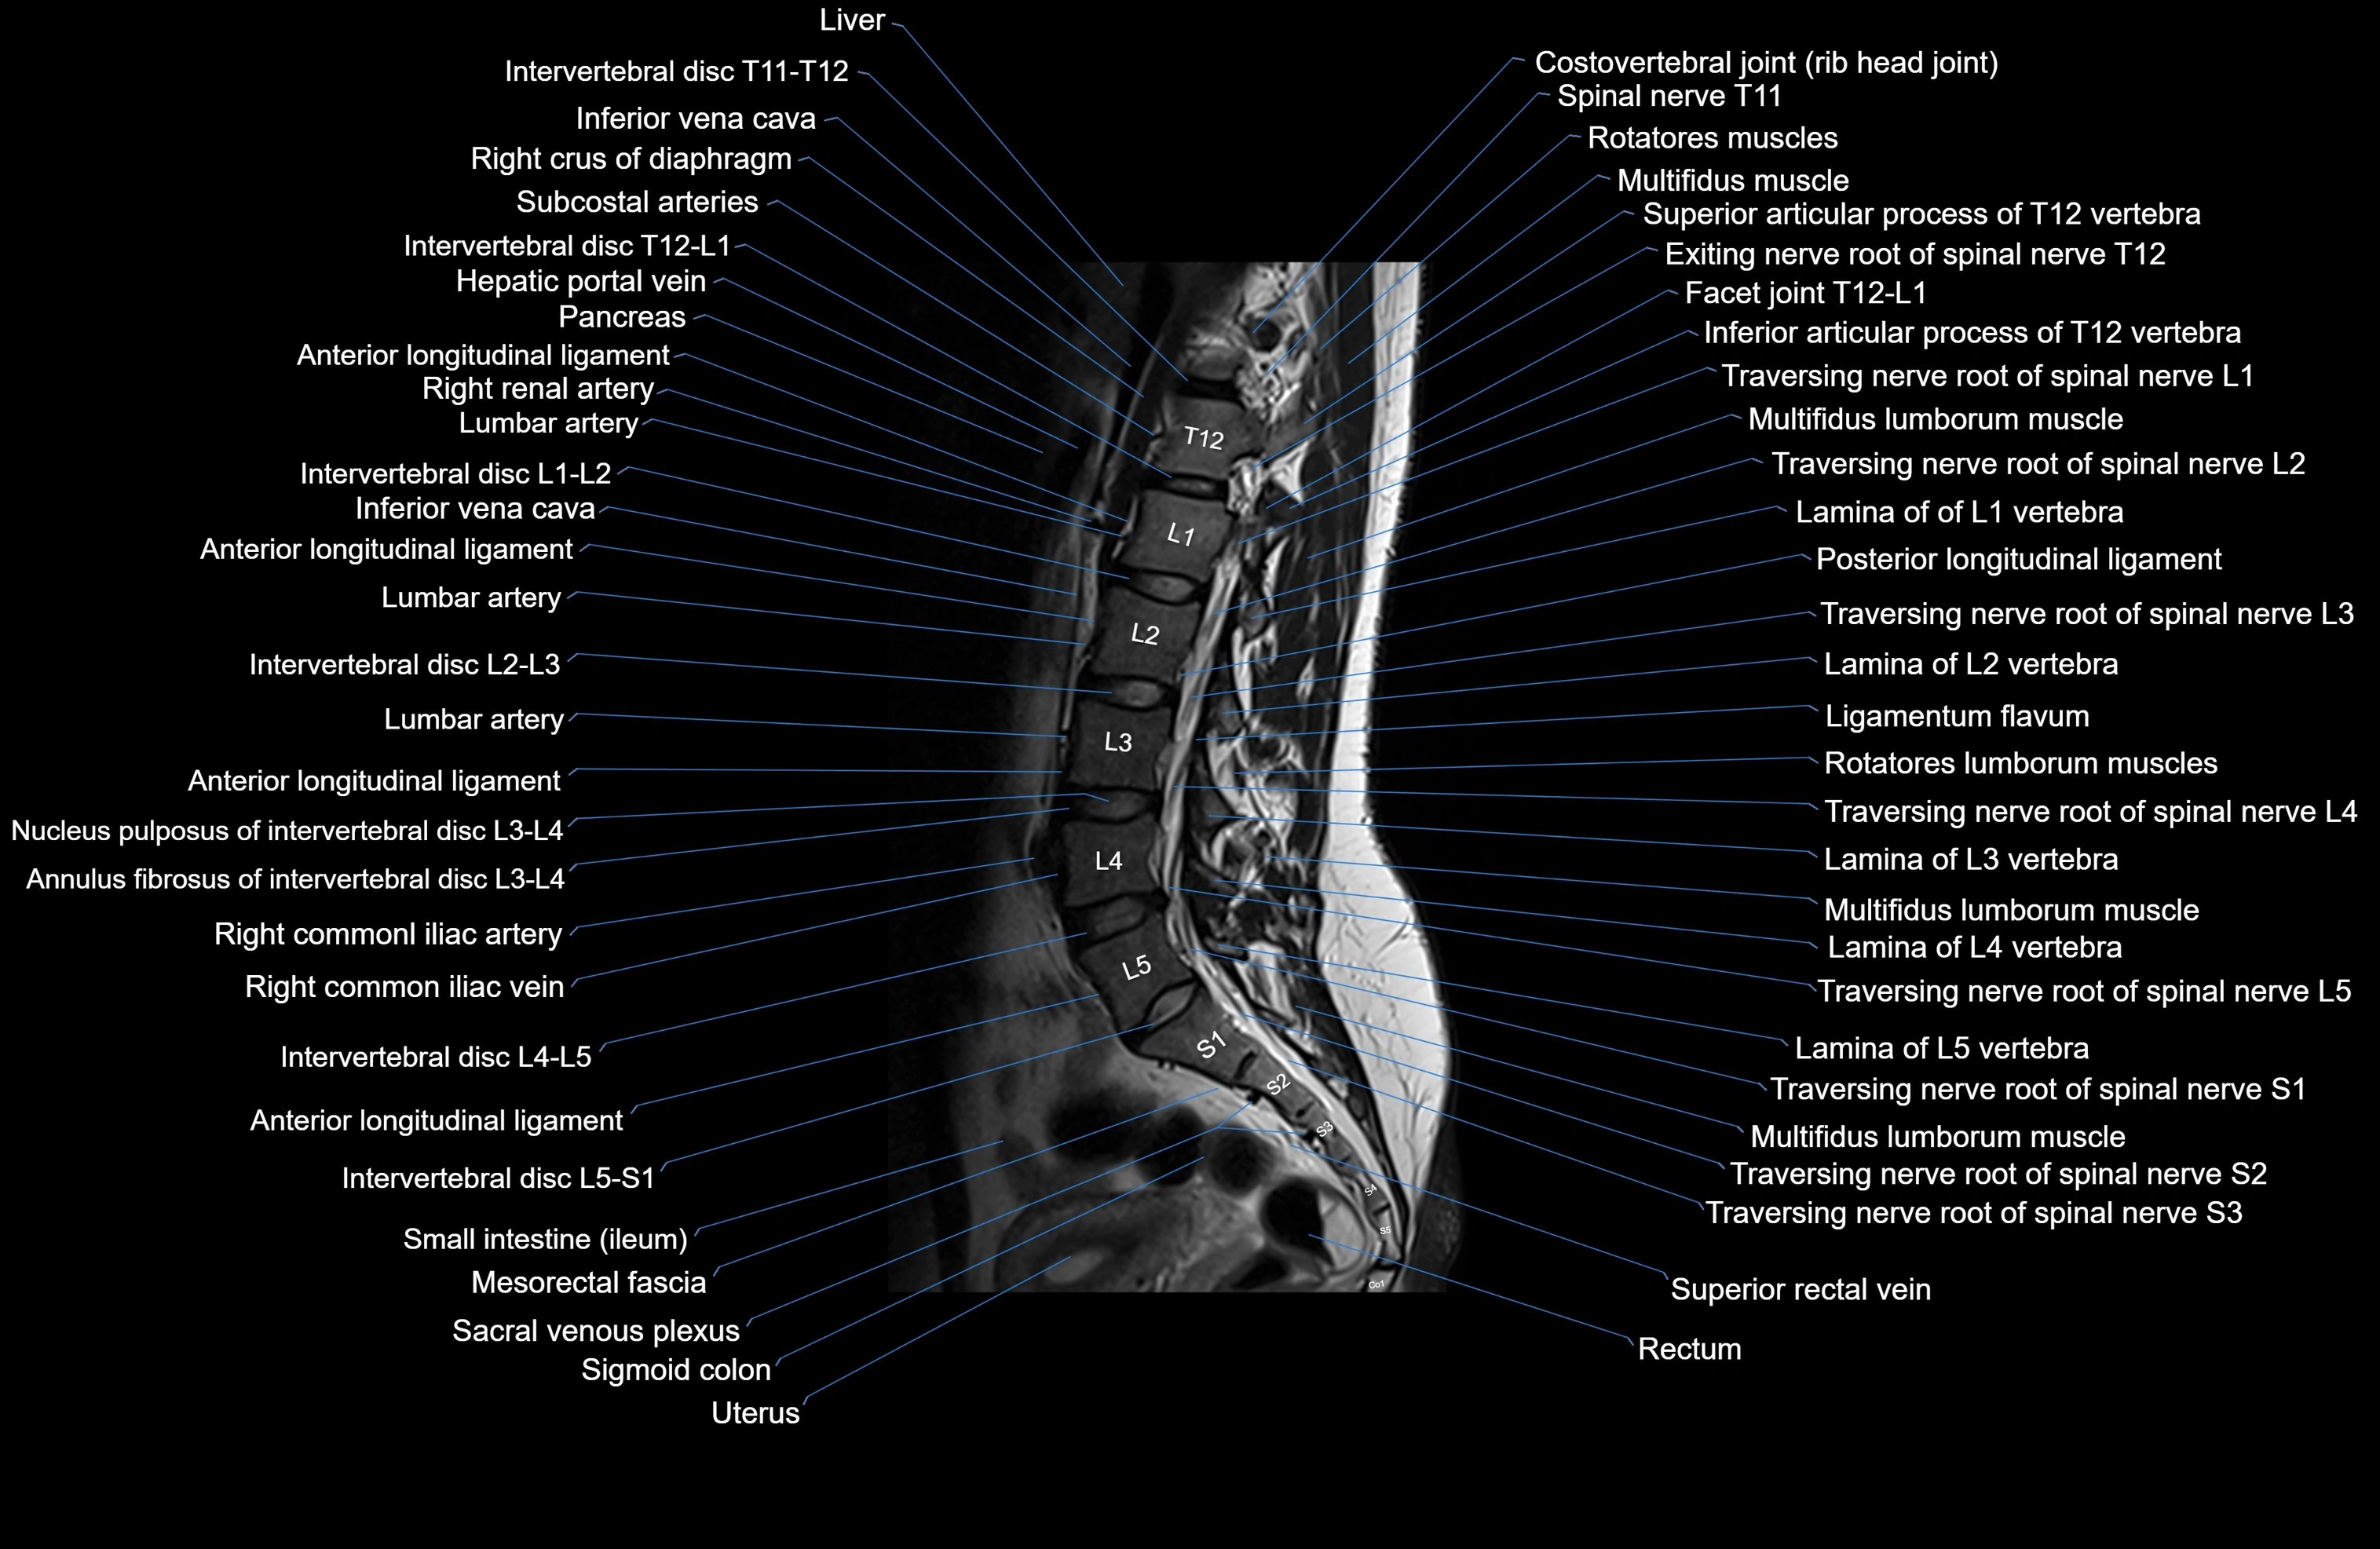

MRI images